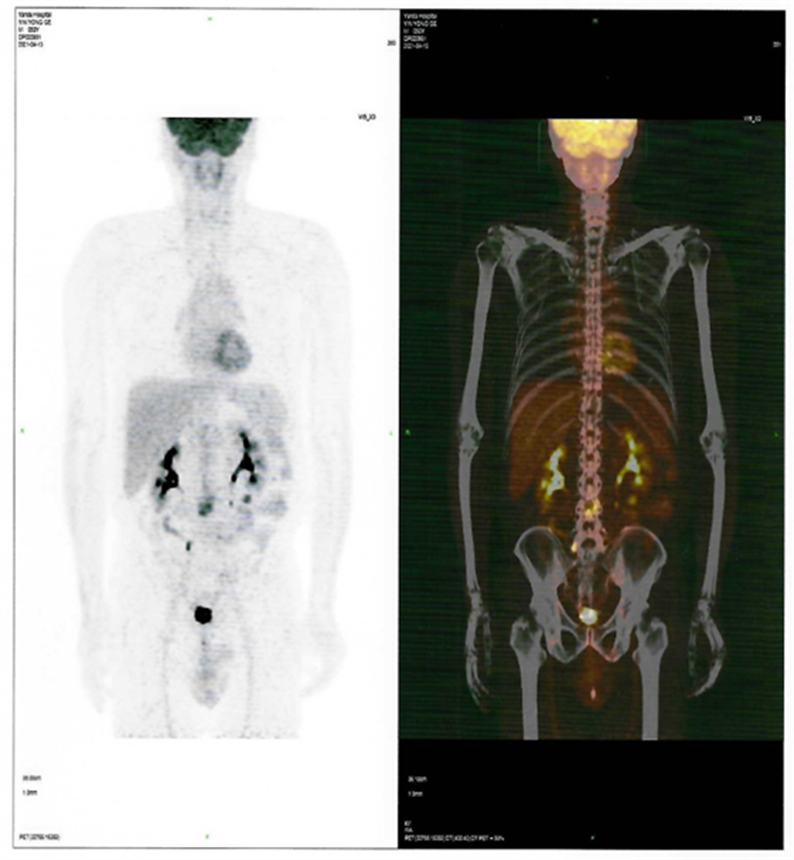

患者CAR-T 前后PET-CT檢查結(jié)果對比圖

CAR-T治療前

CAR-T治療后30天

近日,燕達陸道培醫(yī)院血液科二病區(qū)傳來好消息,一位罹患T細(xì)胞淋巴瘤前期在美國治療復(fù)發(fā)的患者,4月28日,在我院回輸CD7 CAR-T細(xì)胞,5月26日經(jīng)PET-CT檢查,顯示CR(完全緩解)。

回輸后一度出現(xiàn)了一級CRS反應(yīng),癥狀可控,5月26日,回輸后+28天復(fù)查PET-CT顯示CR(完全緩解)。預(yù)祝黃山先生接下來的治療一切順利!